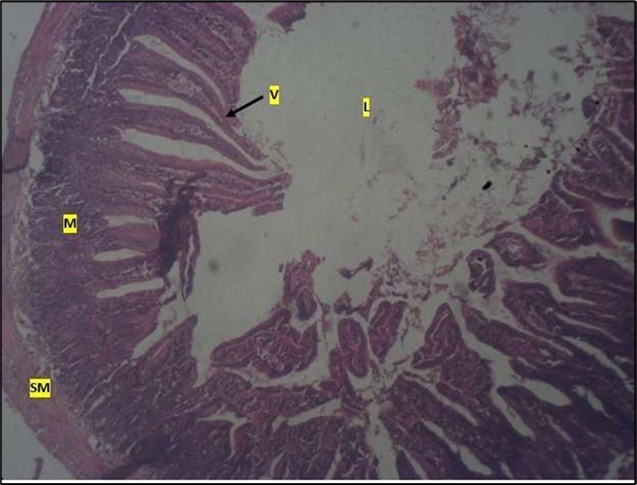

Micrographs of The Small Intestine

Histological examination of the small intestine result in control animals revealed a normal architecture with the red pulp and white pulp with no pathological observation Figure 2. Administration of Abelmoschus esculentus at low dose shows an increased cellularity with numerous cells in the Mucosa and the villi projecting towards the lumen. Focal metaplasia of mucosal cells alongside villous disruption was also observed (Figure 3). The high dose group showed normal cellular architecture with no villous disruption (Figure 4).

Figure 3.Low dose showing numerous epithelial cells in the mucosa (m) with villi projecting towards the lumen (l). The is focal metaplasia of the mucosal cells with villous disruption. smooth muscle layer appears normal. H & E. X40

Figure 4.High dose showing a normal mucosa (m) with villi (v) projecting towards the lumen(l) and underlying smooth muscle layer (sm). No pathology seen